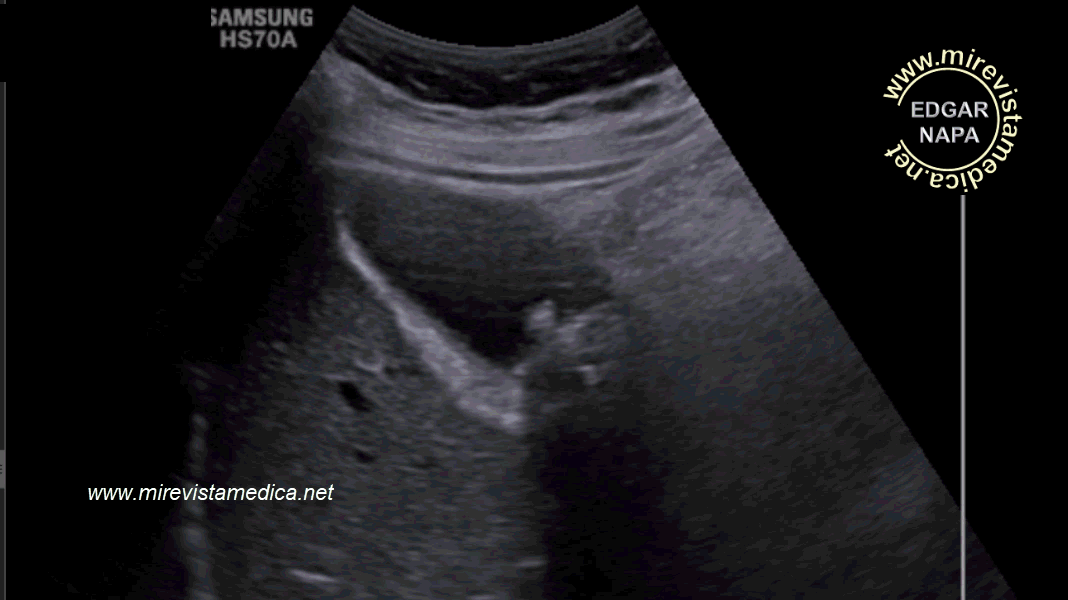

Hallazgos por ultrasonido (US_) :

- imagen hiperecogénica, movil, de márgenes circunscritos que deja sombra acústica posterior (litiasis).

- Signo de Murphy ecográfico. Pain and tenderness with transducer pressure directly over gallbladder.

- Engrosamiento de pared vesicular (se le denomina así cuando es > 3 mm). Hazy delineation of GB wall with echogenic pericholecystic fat.